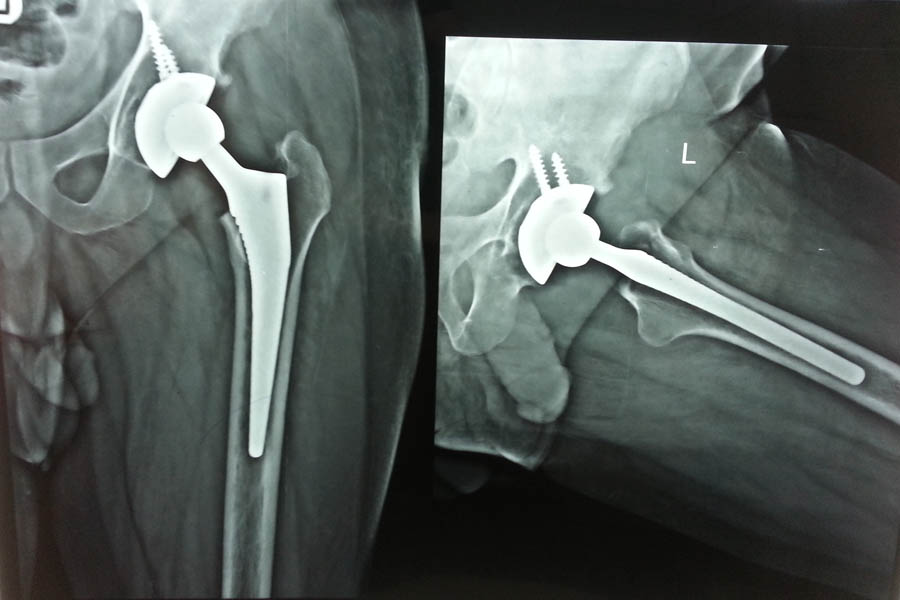

Total Hip Replacement

Difficult Replacement